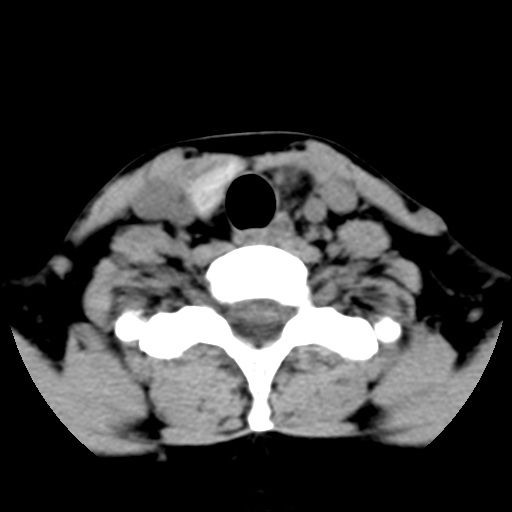

女,44岁,左颈部肿块伴疼痛两个月。患者不能做增强扫描。

左侧甲状腺明显肿大,密度不均匀性减低,正常之钙化基本消失,残留少许呈云雾状及颗粒状。其边缘不规则、不清晰,与前部联合处正常甲状腺不能分界不清,但尚可与周围其他组织分辨。颈动脉鞘区无明显淋巴结肿大。

多考虑:左侧甲状腺癌。

左侧甲状腺腺瘤或癌。甲状腺周围软组织间隙尚存在,喉软骨未见破坏征象,考虑腺瘤可能性大。

左侧甲状腺明显肿大,密度不均匀性减低,可见明显淋巴结肿大.

考虑:左侧甲状腺癌

左侧甲状腺弥漫性肿大,密度减低,与气管及周围血管等分界清晰,颈部未见明显淋巴结肿大.首先考虑左侧甲状腺瘤;其次考虑甲状腺炎;不排除甲状腺癌可能.

多考虑甲壮腺腺瘤可能性大,周边的脂肪间隙显示尚清楚,未见明显肿大淋巴结.气管未见受压.